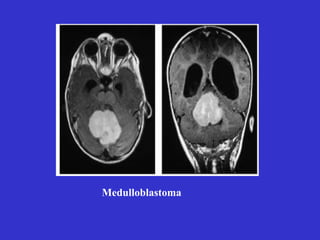

Medulloblastoma• U tiểu não

- U tế bào sao và u

nguyên tủy bào ở trẻ em

- U di căn thường từ phổi

và vú

- U tế bào gai ở trẻ em từ

2-20 tuổi, lành tính và có

nang

- U hố sau (u dây VIII)

chèn ép tiểu não

Medulloblastoma

Acoustic neuroma